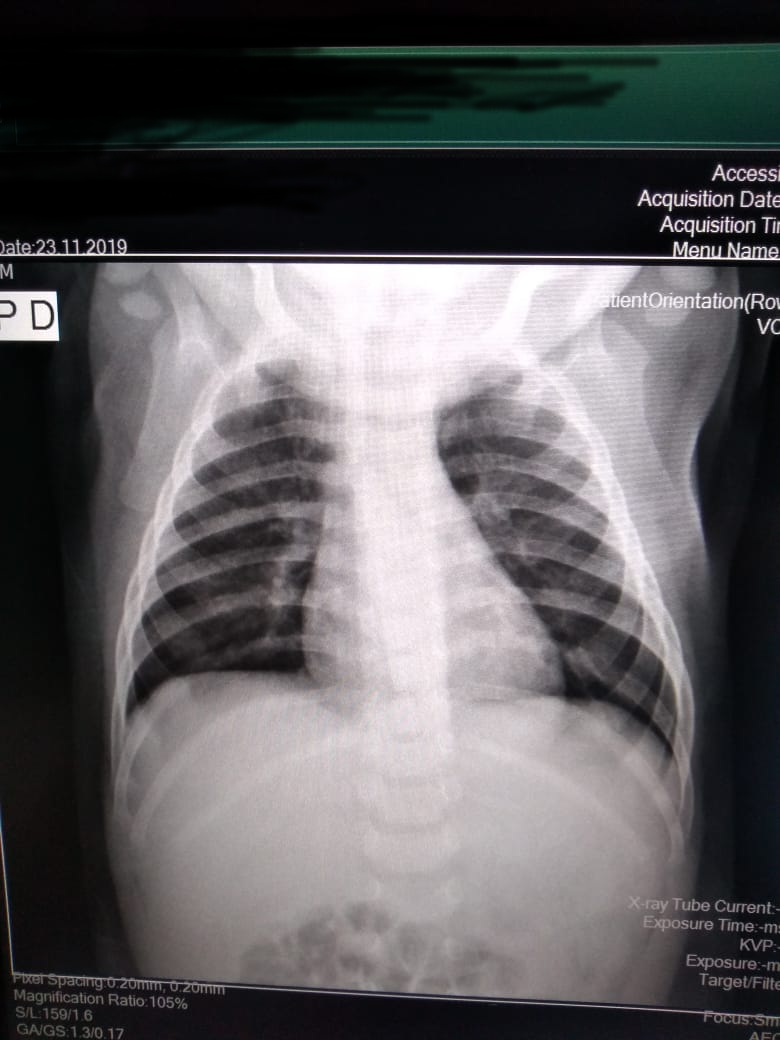

Demanda: Estudo de Caso Clínico (qual o meio de obte-lo: contrato NDA, orçamento?) das análises que fizemos (em anexo) de raio x e tomografia computadorizada obtidos em base pública realizado sob plataforma pública de deep learning com modelo abastecido por datasets públicos de pacientes suspeitos de contágio com covid-19 e outras doenças respiratórias****.

1 - Abrir a plataforma Covid-19, uma base de imagens de raio-X (open data) do Ministério da Saúde de pacientes suspeitos, com resultado POSITIVO para COVID-19, outras doenças respiratórias.

3 - Treinar o Modelo Mellieri Human de Rede Neural Convolucional para detectar o COVID-19 e outras doenças respiratórias em imagens de raios-X e tomografia computadorizada.

4 - Notamos que um paciente pode ter um misto de complicações respiratórias (Covid e Pneumonia por exemplo).

Qual impacto disto nas pesquisas e soluções para combate ao covid-19 como vacinas em função do estágio da doença a exemplo do metadados anexos já que os diagnósticos podem ser únicos para cada paciente no tempo?